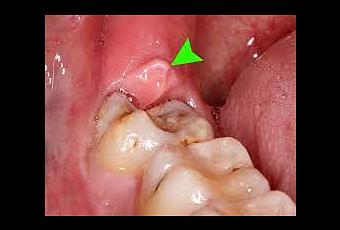

Todo el mundo oye hablar de sacar las muelas del juicio a los demas, pero hasta que no te toca, pos ni idea de como va, y ese era mi caso, ni idea. Mi Invisalign me cubre hasta la muela inferior asi que temia que fueran a sacar esa y tener que cambiar algo, pero no, solo eran las superiores. Ambas estaban fuera y por lo visto no suponian mayor problema.

Asi que nada, 3 pinchazos en cada lado de la encia, y a sacar! La primera ha sido por lo visto muy costosa de sacar, se ha resistido, creia que serian asi las dos, pero la segunda en medio minuto estaba fuera. Eso si, la primera ya me ha valido para largo, las he pasado put**...perdon, muy malamente. Con distintos instrumentos van forzando la encia y empujando la muela hacia afuera, hasta que acaba saliendo, pero como digo la primera ha sido dificultosa; La experiencia la verdad muy poco agradable, me han dañado el labio al tener que hacer fuerza con las herramientas y salia con la cabeza como un bombo de tanta presion. Y me temia lo mismo con la segunda muela, que sin embargo en cuestion de segundos ha salido y sin mayor complicacion, cuando me ha dicho "Ya esta", ha sido un alegron jejeje.